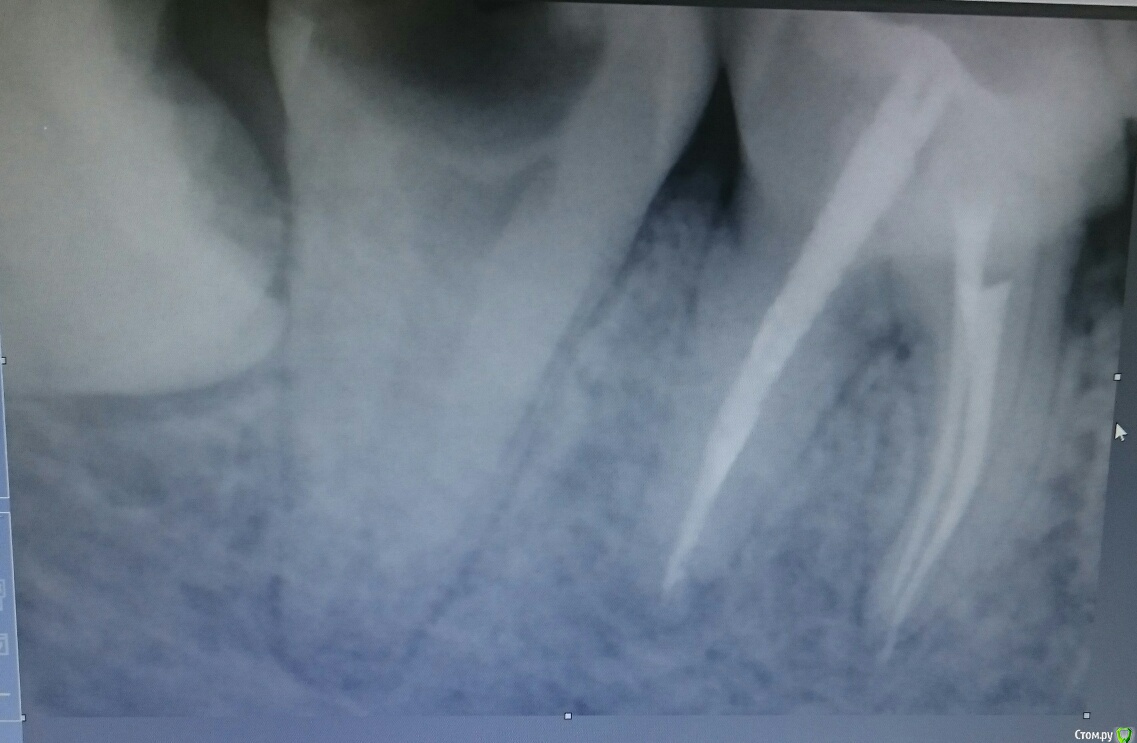

55dantist Опубликовано 21 ноября, 2015 Поделиться Опубликовано 21 ноября, 2015 Пациентка обратилась с острым периодонтитом. Обработка канала протейперами, гипохлор, вода,хлоргексидин. Апекслокатор показал верхушку. Запаковались латеральной конденсацией. А на снимке такая картина ((( Вопрос: Апекслокатор врет? Или на самом деле клиническая верхушка здесь? Кто-нибудь видит продолжение канала?П.с.: КЛКТ не предлагать( нет его по близости)П.п.с:пациентку отпустили с таким пломбированием, через три дня ничего не беспокоит. Ссылка на комментарий

DR.P Опубликовано 21 ноября, 2015 Поделиться Опубликовано 21 ноября, 2015 Скорее всего в этом месте было латеральное ответвление, вот апекс и пищал. Какой силлер? И почему вода? Ссылка на комментарий

DmitrySH Опубликовано 21 ноября, 2015 Поделиться Опубликовано 21 ноября, 2015 Если нет уверенности в аплоке, то лучше лишний раз с файлами на снимок сходить. Тоже думаю что пищал на широкую латераль. 1 Ссылка на комментарий

dima3M Опубликовано 1 декабря, 2015 Поделиться Опубликовано 1 декабря, 2015 Одновременно работая с Rypex и Моритой заметил, что в таких случаях Райпекс врет чаще (при широких каналах).Рентген и бумажный штифт с "кровяной пробой" помогают точнее локализовать апекс.( и в случве конфликта, тьфу тьфу тьфу...не снимок ли будет критерием оценки результата?) Ссылка на комментарий